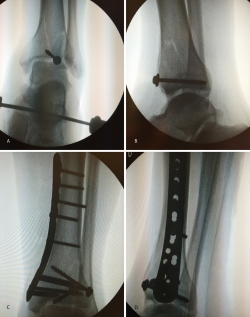

3. Fractura de tipo C: reducción artroscópica, fijación de la epífisis con tornillos canulados y fijación final de la epífisis a la diáfisis por técnica MIPO.

En este caso, es esencial observar las Rx con y sin tracción que nos indican cómo se va a comportar la fractura. Si la fractura es reductible en tracción, es muy probable que podamos realizar una osteosíntesis con restitución completa de la superficie articular. Al realizar la TC, apreciamos la disposición de los fragmentos para marcar una estrategia de reducción bajo control radioscópico y artroscópico, y colocación de los tornillos canulados que fijarán la epífisis distal de la tibia.

Posteriormente, colocaremos la placa en la tibia por vía MIPO realizando una incisión interna, separando la vena safena y deslizando la placa que se fija de manera provisional. Tras comprobar por radioscopia la buena posición del implante, se realiza la fijación definitiva con los tornillos que consideremos adecuados. En el caso de que tengamos que usar un fijador, este sustituye a la placa interna (Figuras 17 a 20).

Figura 17. Caso 3: fractura tipo C. Radiografías sin tracción y con tracción comprobando la reducción.

Figura 18. La tomografía computarizada muestra los fragmentos principales de la fractura, estando desplazado el Tillaux que se reduce con la tracción.

Figura 19. Colocación del tornillo en el Tillaux con la extremidad en tracción y posteriormente la placa MIPO (minimally invasive plate osteosynthesis).

Figura 20. Radiografías postoperatorias y resultado final con movilidad completa en flexoextensión del tobillo.